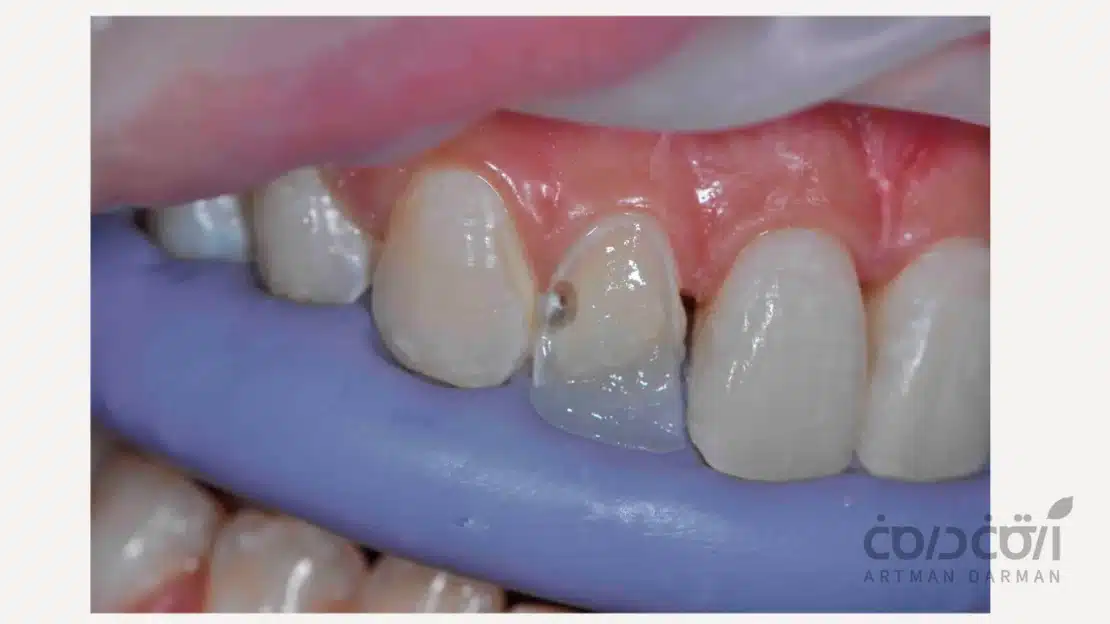

شکستگی های وسیع تاج

گاهی بر اثر ضربه یا فشار ناگهانی، نیمی از تاج دندان می شکند اما ریشه کاملا سالم است. در این حالت، ترمیم دندان شکسته بدون روکش با تکنیک بیلداپ، نه تنها زیبایی را بلافاصله برمی گرداند، بلکه از دستکاری غیرضروری دندان جلوگیری می کند.

اصلاحات زیبایی

شکستگی یا لب پریدگی دندان های جلو، چالشی بزرگ برای زیبایی لبخند و اعتماد به نفس است. در این شرایط، بیلداپ کامپوزیت راهکاری هنرمندانه و محبوب محسوب می شود؛ این روش ساختار آسیب دیده دندان را به گونه ای بازسازی می کند که تشخیص مرز میان دندان طبیعی و بخش ترمیم شده، تقریبا غیرممکن است.